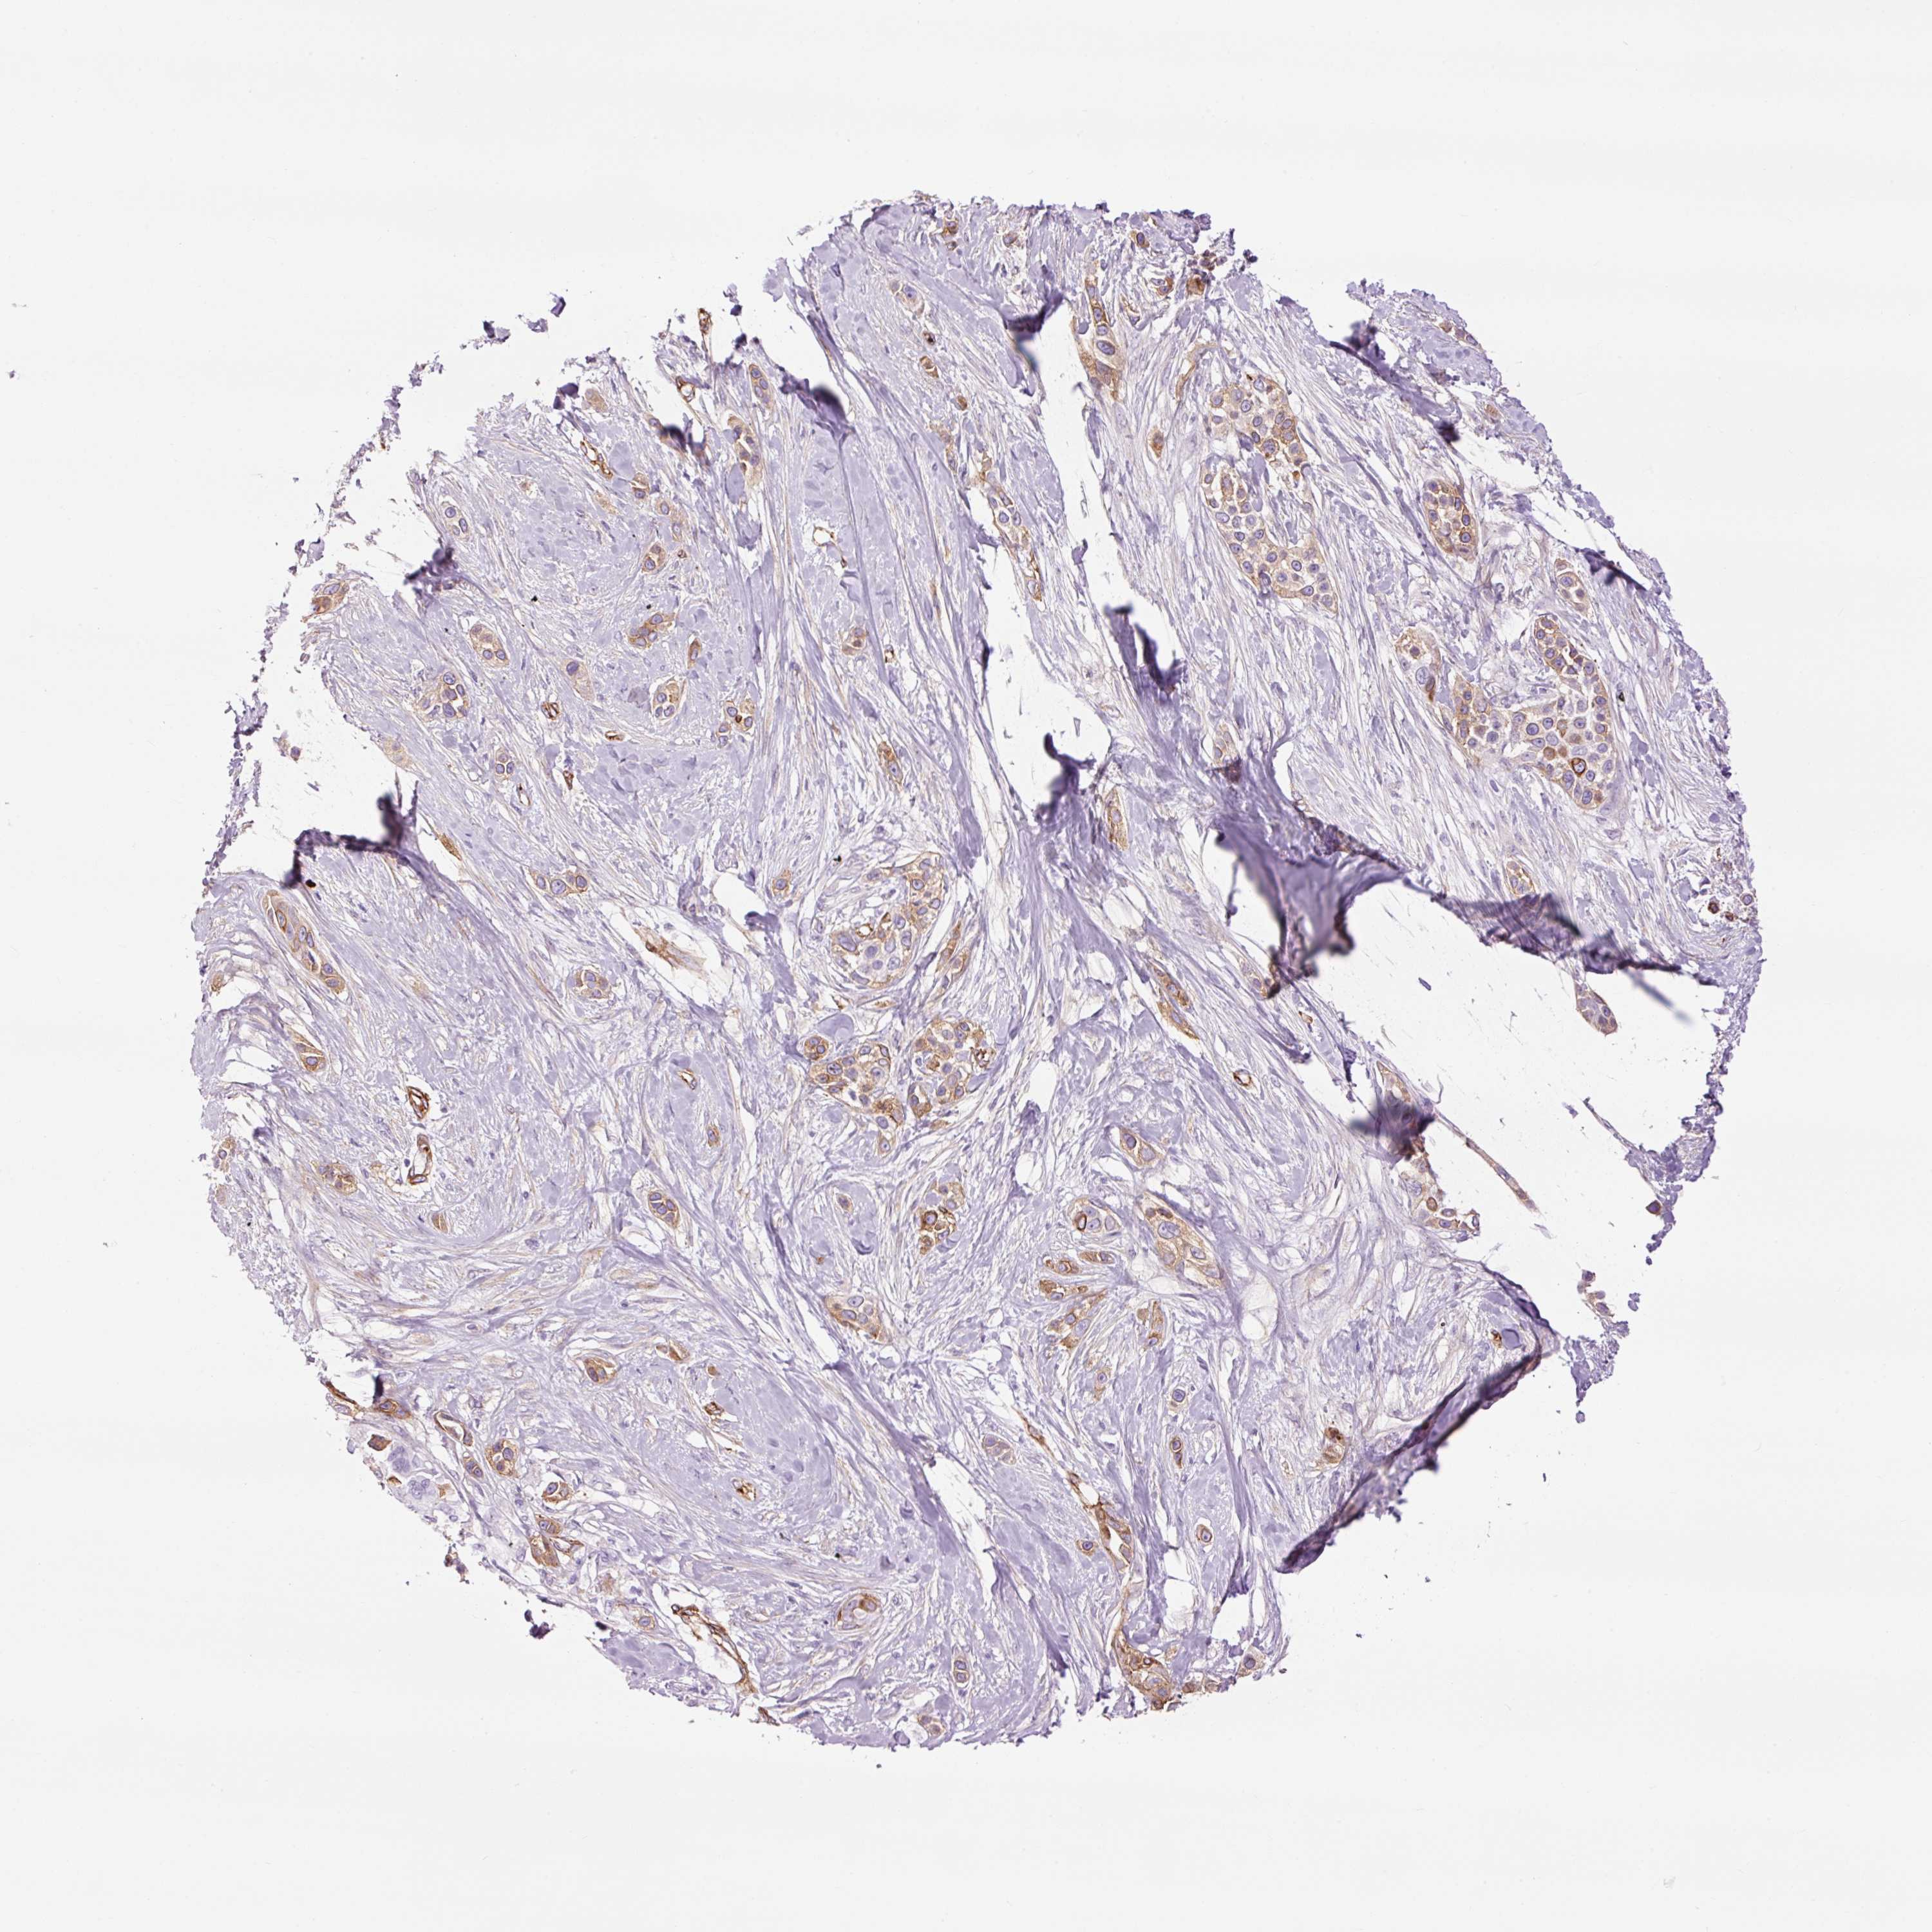

CANCER SKIN CANCER Show tissue menu

Basal cell and squamous cell cancer

SKIN CANCER - Protein expressioni

A mouse-over function shows sample information and annotation data. Click on an image to view it in a full screen mode. Samples can be filtered based on level of antibody staining by selecting one or several of the following categories: high, medium, low and not detected. The assay and annotation is described here.

Antibody stainingi

Antibody staining in the annotated cell types in the current human tissue is reported as not detected, low, medium, or high, based on conventional immunohistochemistry profiling in selected tissues. This score is based on the combination of the staining intensity and fraction of stained cells.

Each image is clickable and will lead to virtual microscopy that enables deeper exploration of all samples and also displays staining intensity scores, fraction scores and subcellular localization as well as patient and tissue information for each sample.

Antibody HPA049326

Antibody CAB003791

Basal cell carcinoma

Squamous cell carcinoma, NOS